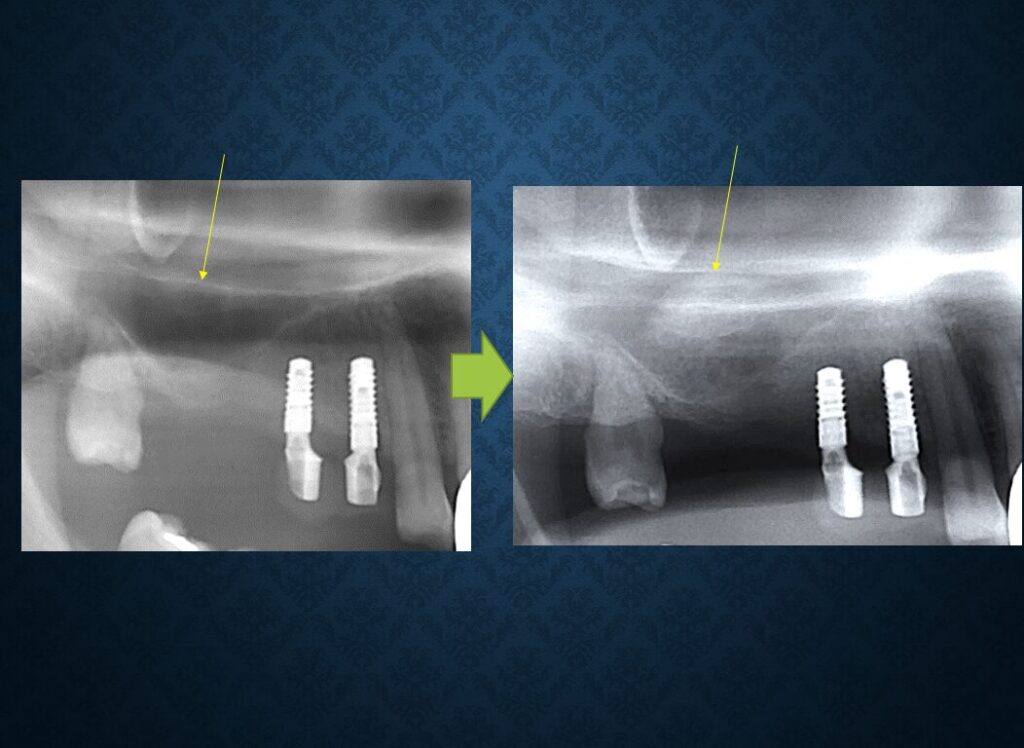

40代フィリピン人男性の方でした。欠損部には入れ歯が入っていました。インプラントに代えて欲しいというご希望でした。職業は会社経営、モデル、英会話教師、ボディービルダー、六本木警察フィリピン語講師、映画俳優など多岐にわたり、日本だけでなく、オーストラリア、台湾、スペインなどを渡り歩いている方でした。多忙を極めていらしたので治療は度々中断しましたが、無事にゴールできました。